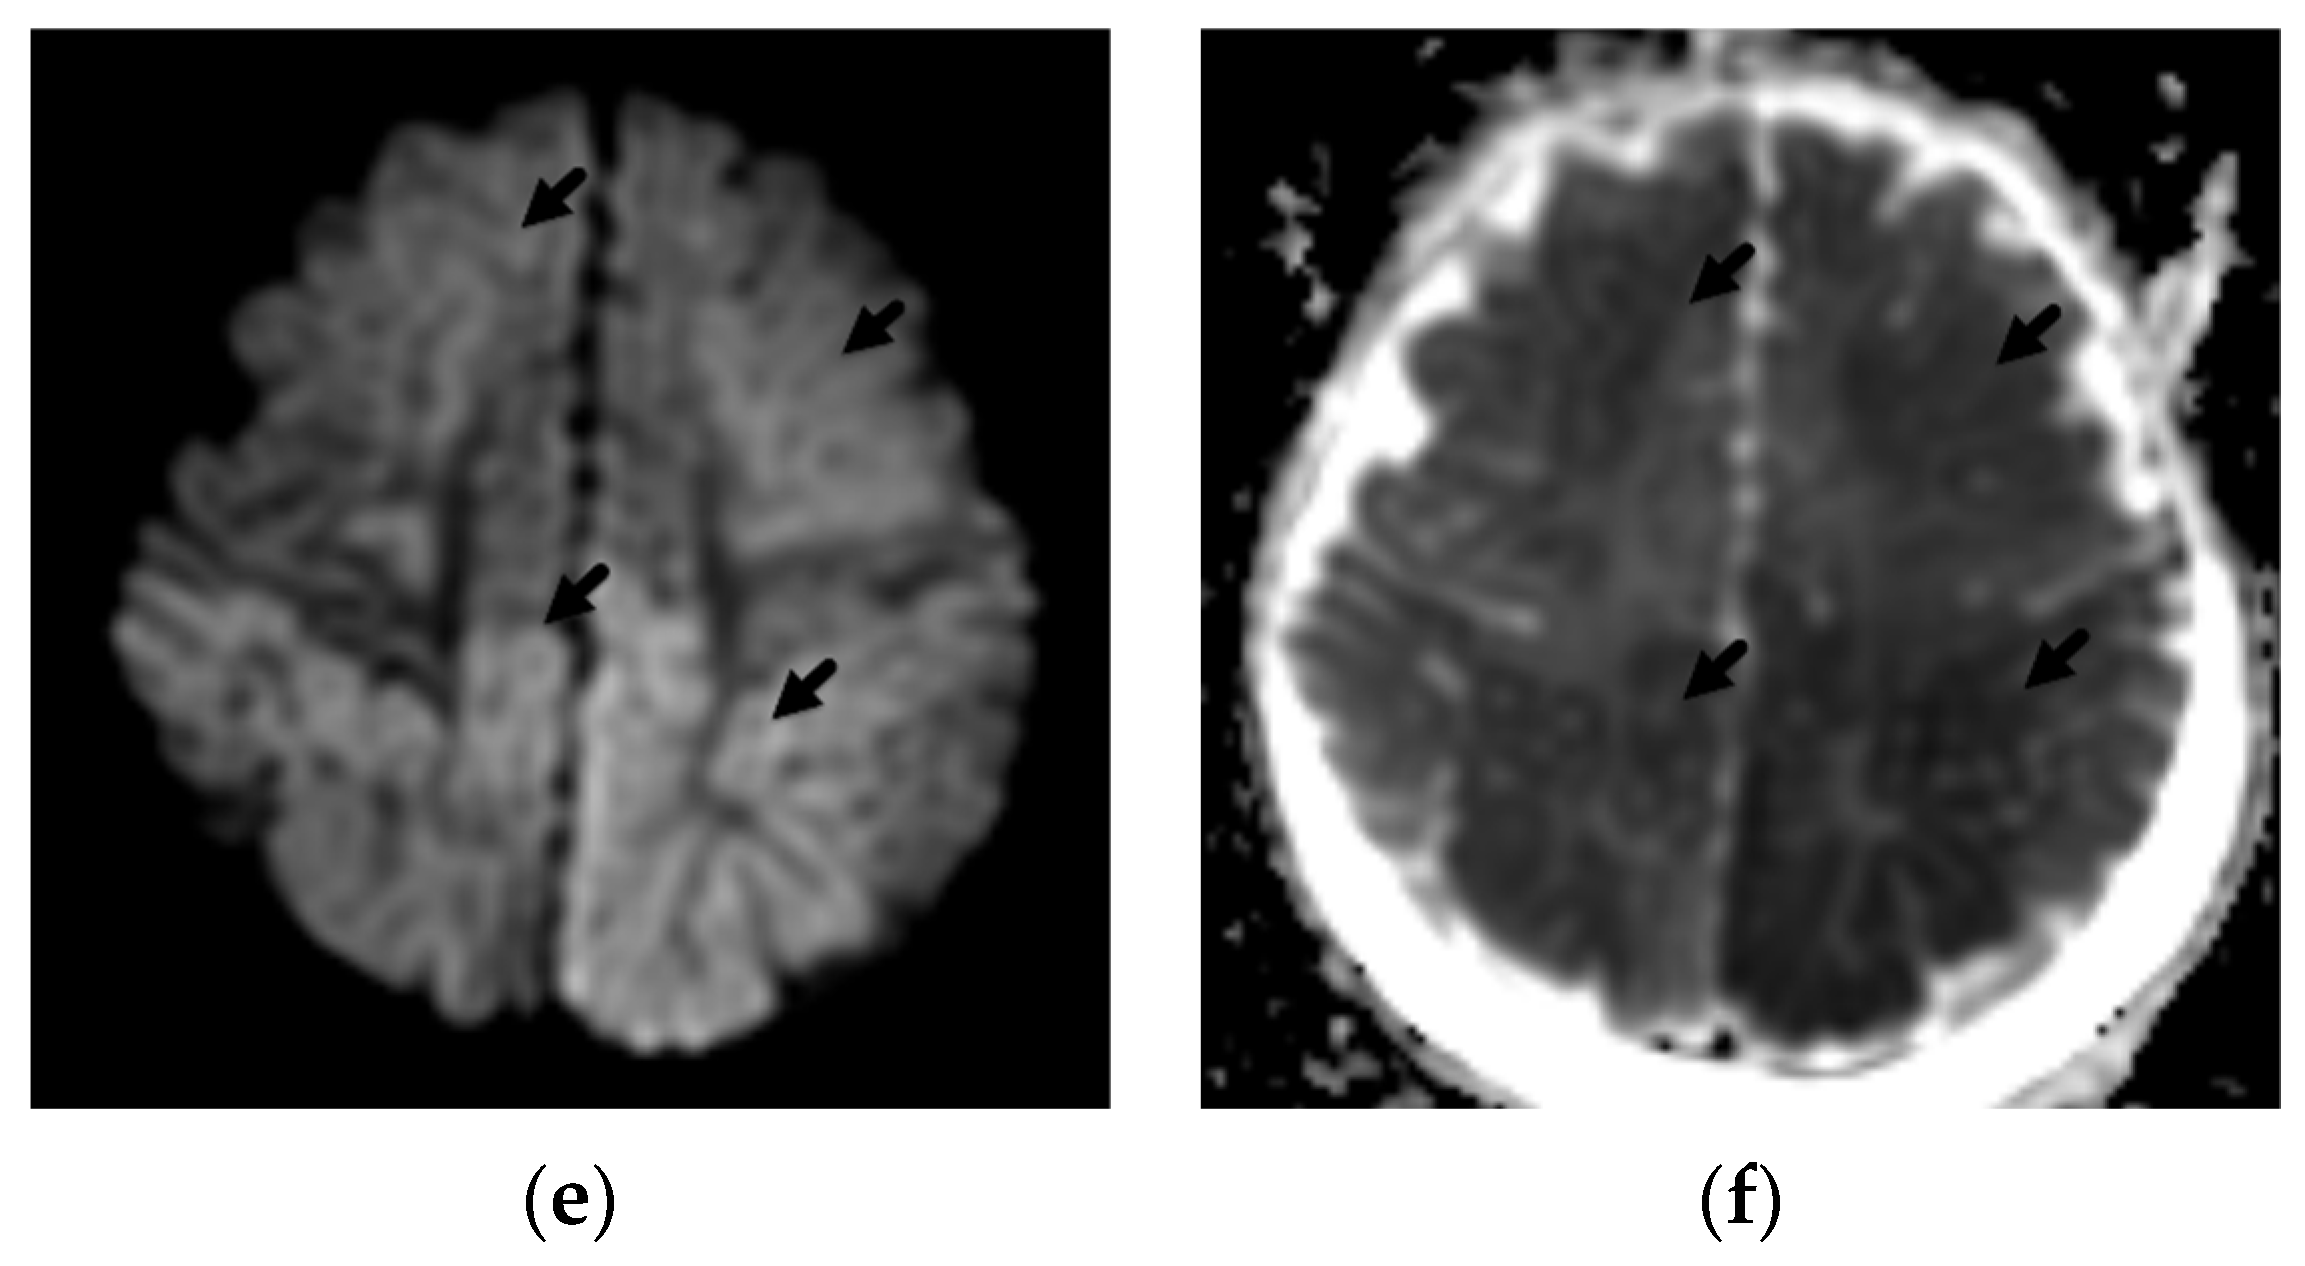

2. Patterns of Diffuse Parenchymal Insults

3. Imaging of Diffuse Insults

4. Focal Parenchymal Insults

5. Imaging Evaluation